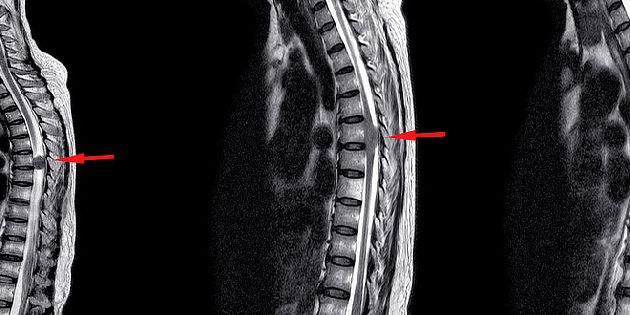

Nádory míchy se vyskytují poměrně zřídka a ve většině případů jsou nezhoubné. Jakmile však dosáhn...